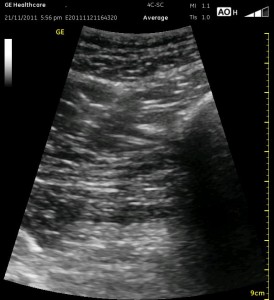

The image above is not an obvious one, and I did that on purpose. You have to get used to the idea that you will not always have a ‘super distinct’ image with this approach, and you will often need to use a number of additional clues to find your target and then to put local around it. I think the only way to really get a handle on being able to identify the basic elements is to look at several images over and over, so I have provided several below for you to use for practice. Note that the sciatic nerve will ‘poke out’ from behind the femur to different degrees depending on your orientation to the femur as well as to how far up or down the femur you go. It will be seen more if you are proximal. See how well you can identify the structures in the images below.